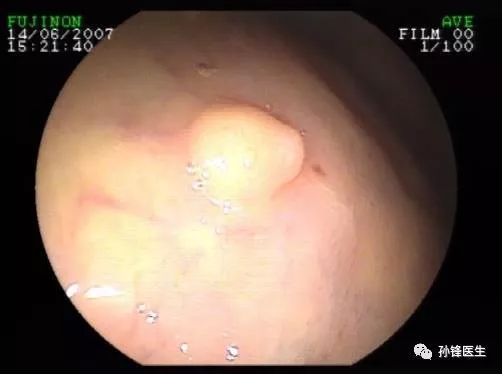

淺二度燙傷通常只影響表皮和真皮層,患者會感到劇烈疼痛、腫脹明顯,并出現局部水皰(這種程度的傷害一般較輕微)。二度燙傷屬于哪種傷害呢?浙江大學行知學院發生一起糾紛,一名女生故意將保溫杯里的開水燙傷了男同學的背部。

急救措施二度燒傷有水皰時,不要把水皰擠破。2.深Ⅱ度燙傷:可能在局部留下一定疤痕,且部位不同留疤概率也不同。一度燙傷表現為皮膚輕度發紅,有一些灼燒感的疼痛,此時應用自來水或涼水沖泡至少15分鐘;二度燙傷伴有一個或多個散在的水泡,燙傷后自來水沖泡的同時應注意不要撕開水泡,以防感染;三度燙傷疼痛沒有那么敏感,可能燒到皮膚的更深層導致碳化。